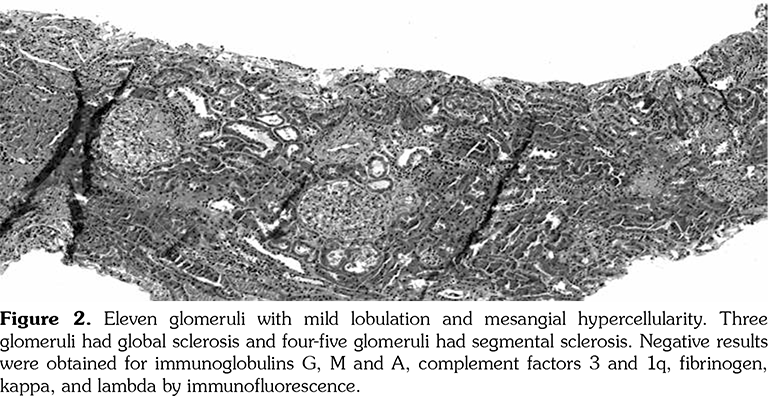

A 14-year-old female patient referred to our clinic with headache and dizziness for two weeks and loss of consciousness for about 10 minutes. On admission, the blood pressure was 90/60 mmHg and all peripheral pulses were palpable. Her body weight was above 97th percentile for her age and body mass index was 33. The fundus examination and other organ systems were essentially normal. Laboratory studies revealed erythrocyte sedimentation rate (ESR) as 108 mm/hour and C-reactive protein (CRP) as 7.5 mg/dL (0-0.8), while other measurements were normal. Urinalysis revealed microscopic hematuria and proteinuria of 31.9 mg/m2/hour in 24-hour urine collection. The cerebrospinal fluid examination showed no abnormalities. Cranial magnetic resonance imaging (MRI) showed multiple millimetric hyperintense deep white matter lesions on T2-weighted imaging (Figure 1). Intracranial and extracranial arteries were normal in magnetic resonance angiography (MRA). Renal biopsy findings were interpreted as FSGS (Figure 2). Patient was considered as cerebral vasculitis and incidental FSGS. Pulse methylprednisolone therapy for three consecutive days was initiated and continued with oral prednisolone. At four years of follow-up, proteinuria decreased to 5-15 mg/m2/hour, and ESR and CRP were normal. Repeated brain MRI and MRA examinations showed no new lesions. Four years later, at the age of 18, on a routine examination, both radial artery pulses were absent and the blood pressure could not be measured. Significant bruit was heard on the left carotid artery. Laboratory studies revealed ESR as 43 mm/hour and CRP as 2.46 mg/dL. Aortic MRA revealed diffuse wall thickening and contrast enhancement in the arcus aorta and its many main branches (Figure 3). Takayasu arteritis diagnosis was established according to the European League Against Rheumatism/ Paediatric Rheumatology International Trials Organisation/Paediatric Rheumatology European Society criteria.[2] Methotrexate was begun, and daily prednisolone was continued. Four months after the diagnosis of TA, left-sided hemiparesis developed. Brain MRI demonstrated a wide cerebral infarct at the right anterior vascular territory (Figure 4). Brain and neck computed tomography angiography showed total occlusion of the right internal carotid artery. Vascular involvement of the right common carotid artery was progressed to preocclusive stenosis. Diameters of the right anterior and middle cerebral arteries were thin and fed by the posterior and anterior communicating arteries (Figure 5). Tocilizumab treatment was started at 8 mg/kg every four weeks. At follow- up with 2.5 years of tocilizumab treatment, the patient's clinical condition improved slightly, and no new symptoms developed. A written informed consent was obtained from the patient.

Renovascular hypertension is the most common renal manifestation of TA; however, proteinuria and nephrotic syndrome are both very rare and usually caused by factors other than FSGS. Four years before the diagnosis of TA, our patient was diagnosed as cerebral vasculitis. In the same period, renal biopsy performed due to proteinuria was reported as FSGS. Cerebral vasculitis and TA in our patient may be coincidental with FSGS but it was supposed that immune complex deposition and vascular lesions caused glomerular ischemia in TA.[7] Kuroda et al.[8] reported a 50-year-old female patient with TA who developed proteinuria and renal dysfunction with glomerulopathy mimicking membranoproliferative glomerulonephritis. They argue that increased vascular endothelial growth factor and interleukin (IL)-6 levels may cause renal disease.

Microvascular involvement might lead to glomerular ischemia and obesity might be an additional factor for developing FSGS in our patient. FSGS is a pattern of histologic injury rather than a disease. In obese patients, elevated plasma levels of leptin through upregulation of transforming growth factor beta 1 may also predispose to glomerulosclerosis.[9]